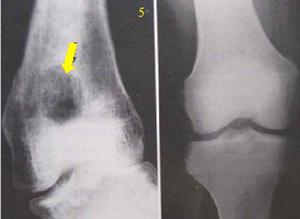

局限性骨膿腫患者表現為局部隱痛、腫、熱,有時毫無不適。一旦體質差,可局部急性發作。X片示乾骺端囊樣破壞區,周圍骨質硬化,直徑1~7cm不等,有時在病灶內可能有小死骨碎片。經抗生素治療和休息可好轉,但不能根治,易復發。

局限性骨膿腫1、X線檢查:表現為長骨幹骺端有橢圓形密度減低區,邊緣有清晰的骨質硬化,病變與鄰近正常骨髓腔境界清楚。需與骨囊腫鑑別。骨囊腫周圍只有薄層成帶狀硬化骨。

2、CT檢查:CT掃描顯示病區為一卵圓形低密度影,其邊界有骨質硬化環。

X線片表現為骨端有局限性密度減低區,其周圍骨質有炎性反應性增高陰影,且與周圍骨質分界不清一般多無骨膜反應及死骨。此種狀態應與骨囊腫鑑別後者主要顯示為囊腔周圍只有薄層帶狀硬化骨。